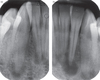

Vertical root fracture on X-ray – diagnosis?

• Fractura verticalis radicis dentis (vertical root fracture).

• Treatment: Extraction